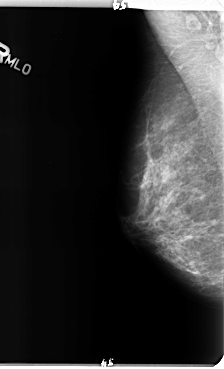

B_3150_1.RIGHT_MLO

RIGHT_MLO LINES 4792 PIXELS_PER_LINE 2912 BITS_PER_PIXEL 12 RESOLUTION 50 NON_OVERLAY